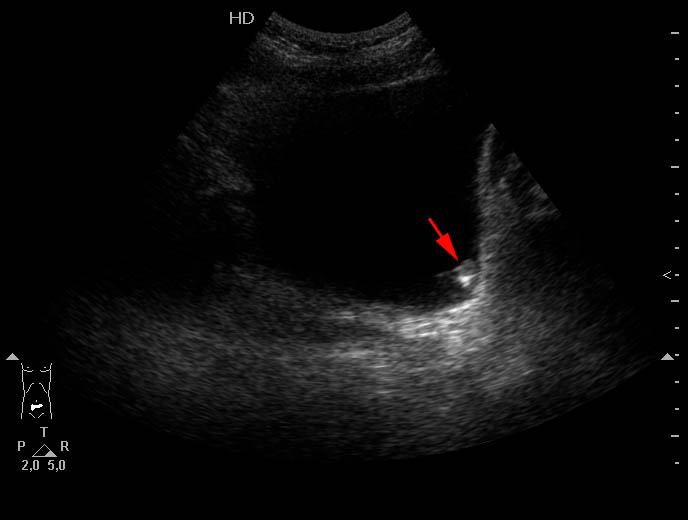

Пожилой мужчина, жалоб нет.

Маленькая папиллярная опухоль (с инкрустацией) левой стенки мочевого пузыря.